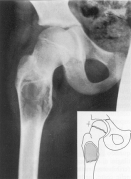

LUXAŢIA CONGENITALA A sOLDULUI apare în cursul vietii intrauterine sau în primele luni de viata, mai ales la fetitele nascute în prezentatie pelviana.

La copilul care nu a umblat

Femurul de partea luxata este mai subtire si mai osteoporotic;

Diafiza femurala este departata de oasele bazinului

În luxatia unilaterala este o asimetrie între cele doua extremitati superioare

Cavitatea cotiloida este aplatizata (aspect de farfurie întinsa)

Unghiul de înclinatie al acetabulului este sub 30°. În luxatia congenitala de sold acest unghi este marit.

La copilul care a umblat în afara de semnele radiologice descrise, se mai constata urmatoarele:

Nucleul osos al capului femural apare mai târziu, chiar la doi ani (în mod normal la 8-10 luni);

Nucleul epifizar de partea luxata este mai mic decât în partea sanatoasa;

Cavitatea cotiloida de partea luxata are forma unei farfurii întinse, este alungita si foarte putin adânca;

Arcul cervico-obturator este întrerupt de partea luxata.

În mod normal, osificarea ramurilor ischiopubiene se face la 5 - 6 ani; în caz de luxatie se produce tardiv dupa vârsta de 7-8 ani.